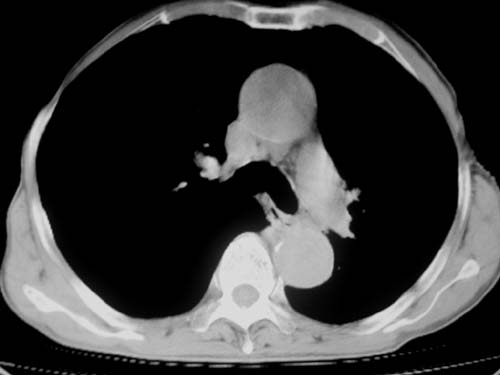

标题: CT19736:男,76岁,咳嗽,胸痛 [打印本页]

标题: CT19736:男,76岁,咳嗽,胸痛

支持左上肺周围型肺癌性并空洞形成伴胸椎转移。

左上沟癌空洞形成并胸椎转移。

考虑癌性空洞并胸椎转移。

空洞内壁有多发结节,支持癌性空洞。

支持左上肺周围型肺癌并空洞形成伴胸椎转移。z左下肺炎

左上肺癌性空洞伴胸椎转移。